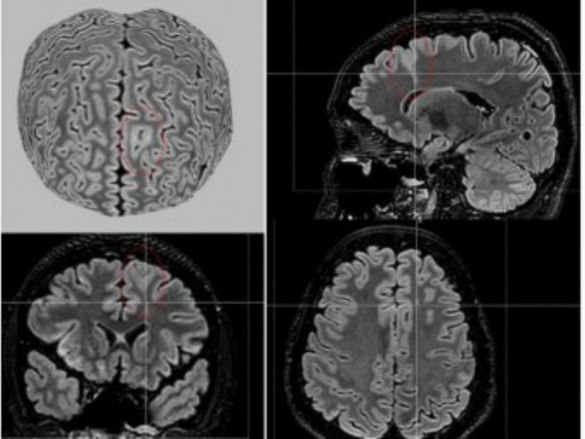

A partir de técnicas de aprendizado de máquina e da análise de dados de ressonância magnética de 1.185 participantes – incluindo 703 pessoas com displasia cortical focal e 482 controles – a ferramenta, denominada MELD Graph, conseguiu detectar as anormalidades a partir de varreduras nas imagens cerebrais.

A ferramenta, cujo algoritmo está disponível publicamente, detectou 64% das anormalidades cerebrais ligadas à epilepsia que os médicos radiologistas não haviam detectado. Com isso, a expectativa é que a MELD Graph possa atender a mais de 4 milhões de pessoas em todo o mundo que convivem com esta causa de epilepsia.

Imagem – Reconstrução de imagem de ressonância magnética mostrando uma lesão sutil de displasia cortical focal (indicada pelo círculo vermelho) em criança com epilepsia refratária a medicamentos (crédito: Laboratório de Neuroimagem/BRAINN/Unicamp)